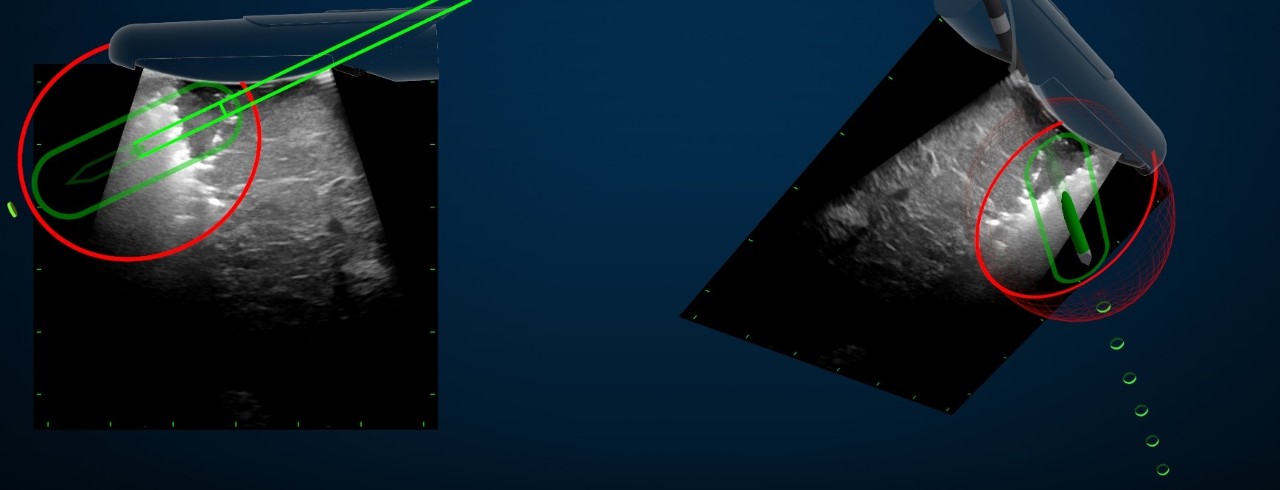

New technology provides navigation in three dimensions as a supplement to static ultrasound imaging. Using an electromagnetic field generator and spatial sensors, a real-time augmented reality image gives the surgeon more detailed information on where the tumor is located.

Featured photo at top: The Medtronic navigation display provides more detailed information to help guide a surgeon during a liver cancer ablation procedure performed at the University of North Carolina at Chapel Hill. Photo/David A. Gerber.